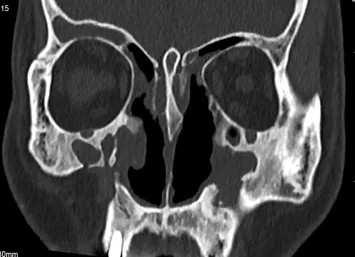

术后

术后,张大爷被安全送回病房。在医护团队的精心治疗和护理下顺利恢复,术前那些困扰他十年的鼻塞、流脓涕、头痛头晕、眶周胀痛不适等症状得到了显著改善,精神状态一天比一天好,脸上重新绽放出笑容。